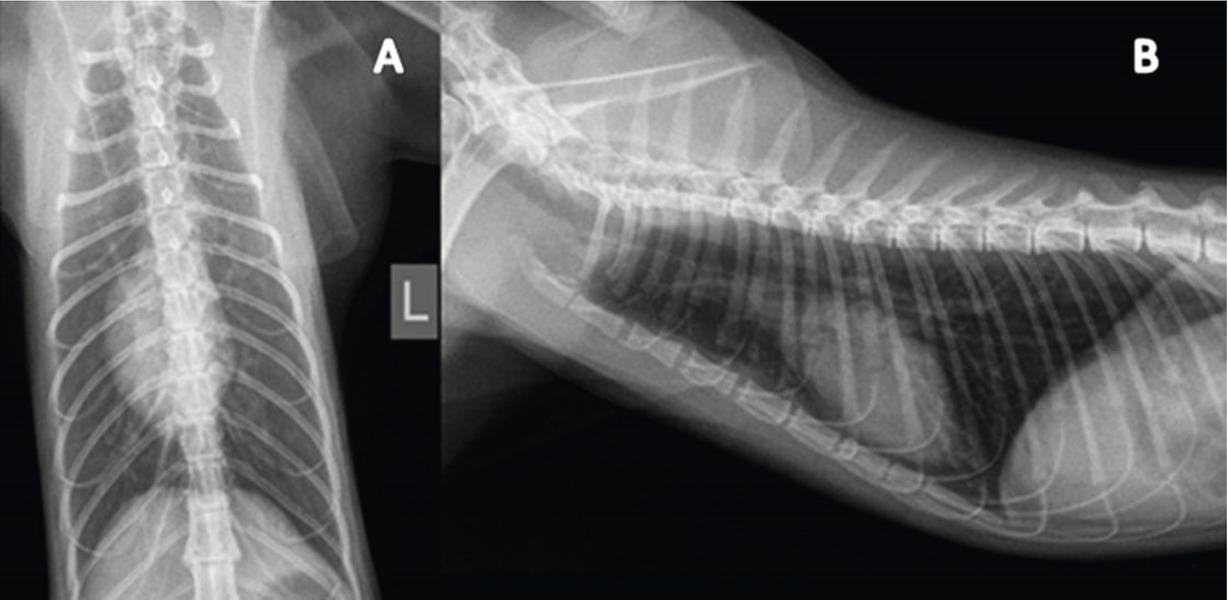

X-rays of the cats with Capillaria aerophila infection have a typical mild lung pattern across the pulmonary fields and is characterized by mild bronchial and alveolar changes and a mild reticular interstitial picture (Fig. 3) We present radiograms of the ventrodorsal and right lateral thoracic X-rays of 7 cats with C. aerophila infection. Four of them had bronchopneumonia with a mild reticular interstitial pattern or with complex lung pattern which was visible across the pulmonary fields, characterized by bronchial and alveolar changes and increased interstitial opacity due to bacterial bronchopneumonia, or viral bronchopneumonia complicated with the secondary bacterial infection, pneumothorax, edema pulmonum, bronchial wall thickening, emphysema, atelectasis, tracheal collapse, an enlargement of the pulmonary artery and pulmonary hypertension. Those changes were followed by respiratory clinical signs due to: tachypnea, dyspnea, abdominal breathing, and end-inspiratory crackles upon auscultation (Fig. 4).

(A) ventrodorsal and (B) right lateral thoracic X-rays of a two-year-old male cat with Capillaria aerophila infection. A complex lung pattern is visible across the pulmonary fields, characterized by bronchial and alveolar changes and mild reticular interstitial pattern, with the symptoms of the respiratory signs due to; tachypnoea, dyspnoea with abdominal breathing, and end-inspiratory crackles upon auscultation.